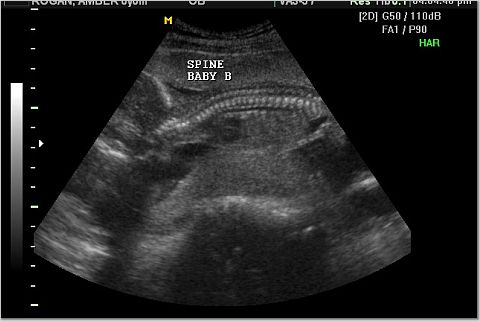

Baby A and Baby B Spine